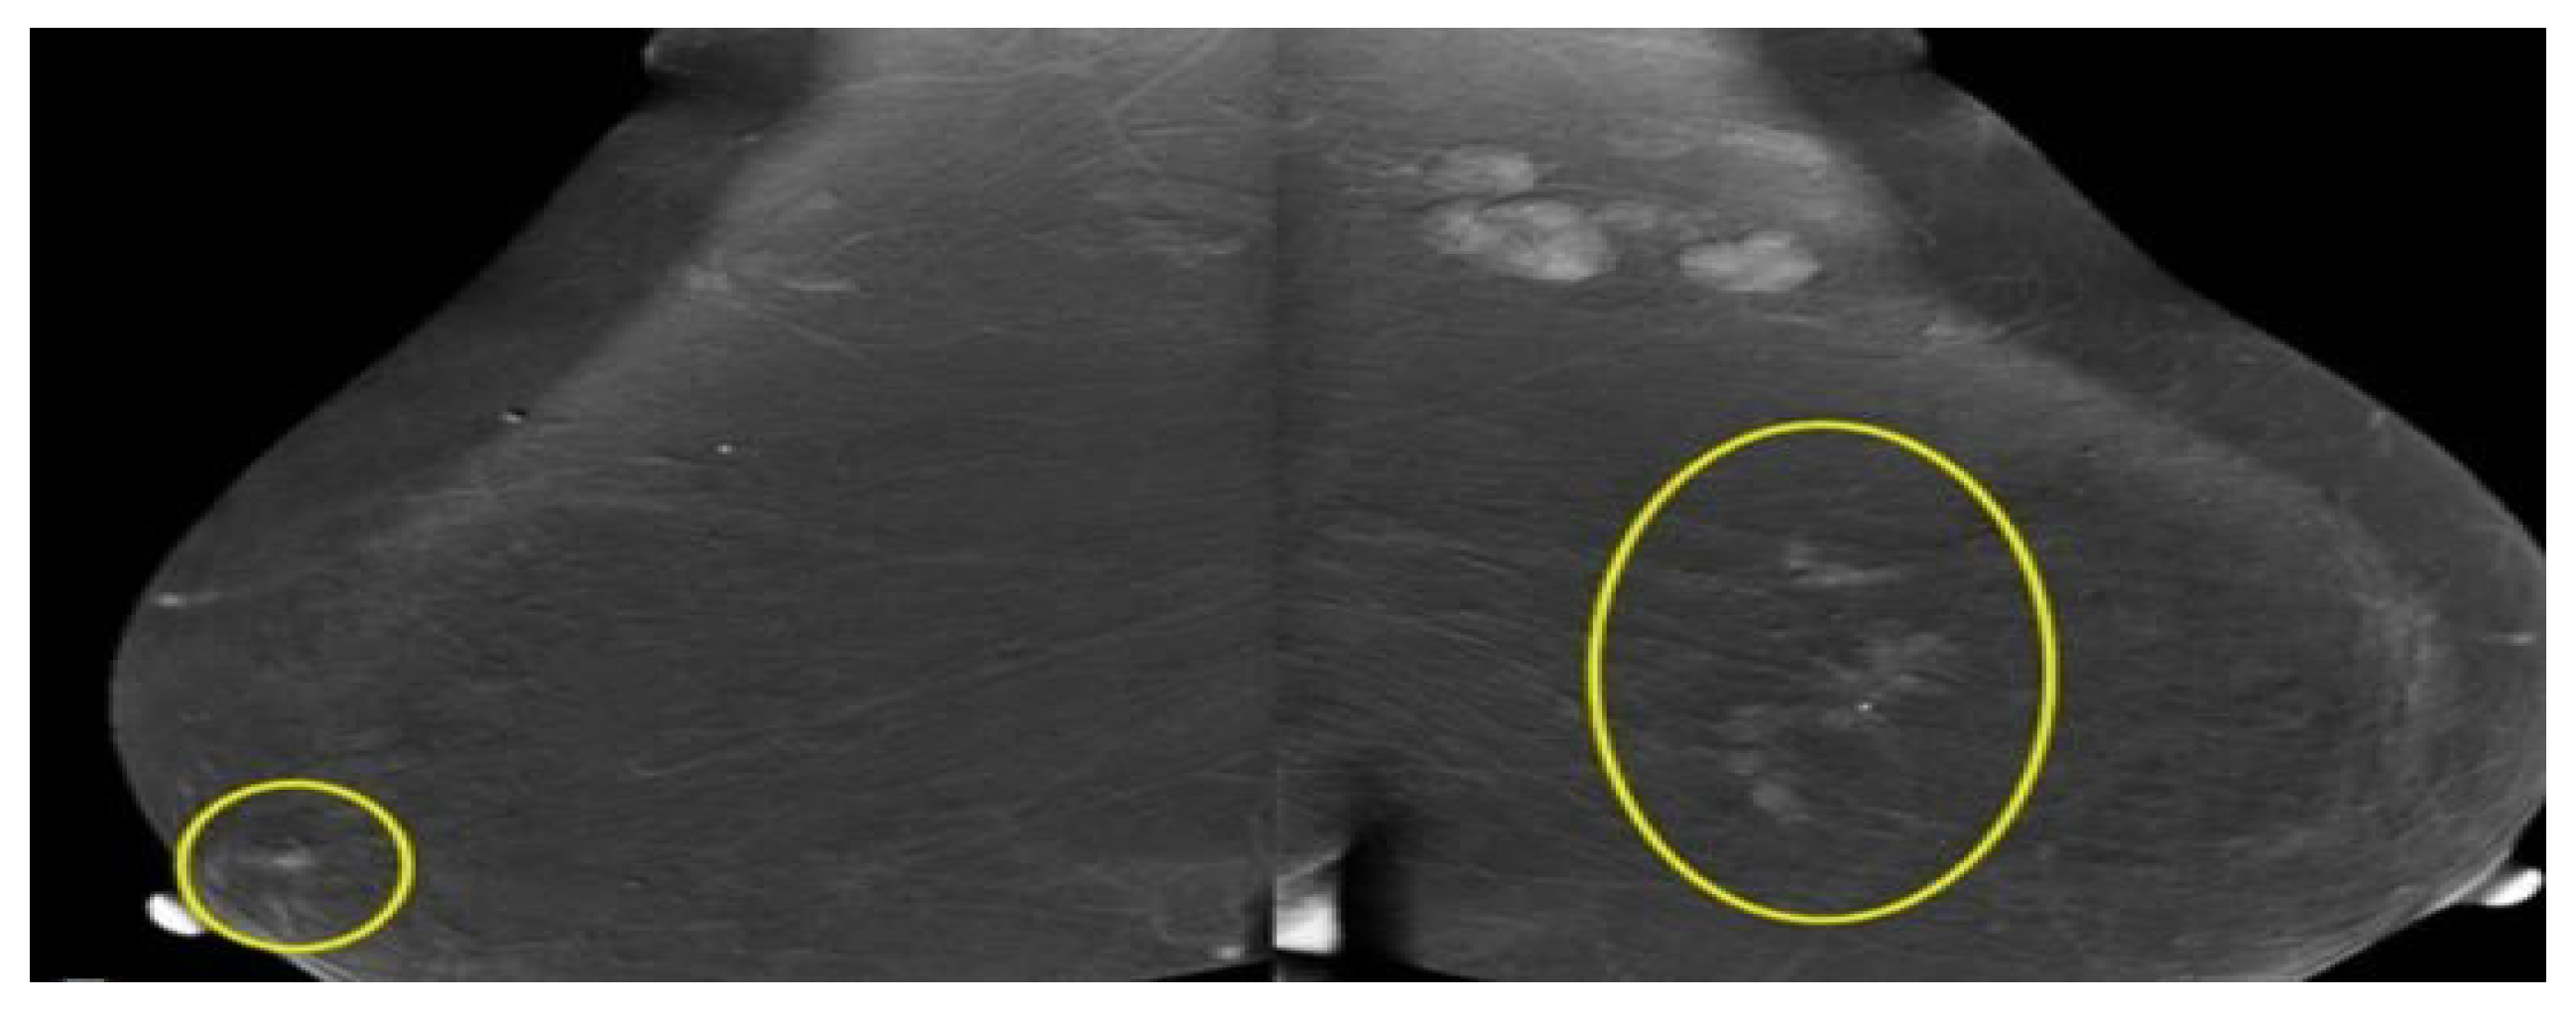

2.1.2. Mammography

- Sani, L.; Vispa, A.; Loretoni, R.; Duranti, M.; Ghavami, N.; Sánchez-Bayuela, D.A. Breast lesion detection through MammoWave device: Empirical detection capability assessment of microwave images’ parameters. PLoS ONE 2021, 16, e0250005. [Google Scholar] [CrossRef]